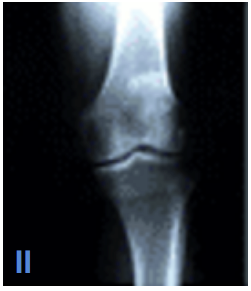

What are some of the characteristics of Kelgren and Lawrence Level II OA?

A

Identifiable osteophytes

Joint space still maintained (mild)